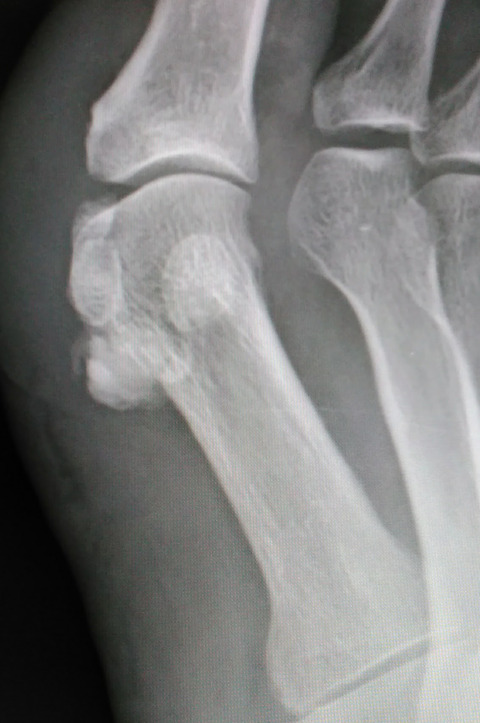

しかし、斜位像では、種子骨よりも中枢側にはっきりとした石灰沈着象を認めます。これは、痛風ではないかもしれない・・・。

身体所見では、母趾MTP関節を背側から触っても圧痛はないようです。ただし、MTP関節足底側のやや中枢側に激烈な圧痛点があります。

足部の側面像を撮影して、確定診断にいたりました。長母趾屈筋腱に発生した石灰沈着性腱炎です。う~ん、痛風発作と非常に紛らわしい。